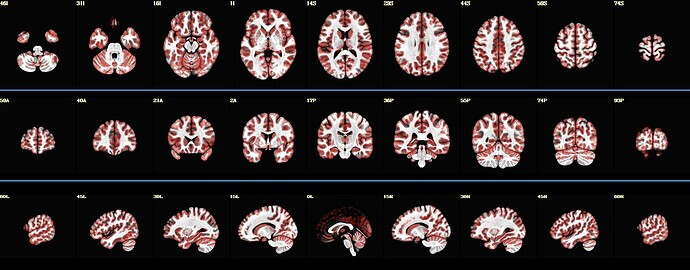

Here is what i can achieve so far :)

Here is the function so far :

https://github.com/sboylan/BOLD-ASL_toolbox/blob/main/plot_brain_maps.sh